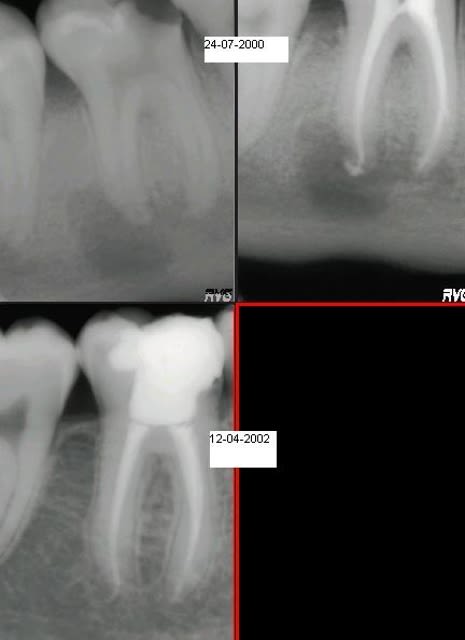

En voilà un qui traine sous le coude.......

je l'ai sorti car je l'ai revu aujourd'hui, soit 8 ans après, et la dent est tjs là. Pas de rx d'aujourd'hui car je suis en panne de RVG (je suis retourné dans la chambre noire....)

oublié le document......désolé

même patient?

dudiarz

Voui

dudiarz, nickel, mais j'imagine que c'est une endo conduite dans les règles de l'art, avec digue à minima (4% d'entre vous, c un bruit qui court).L'exception. ça fait toujours plaisir à voir de tels résultats!!